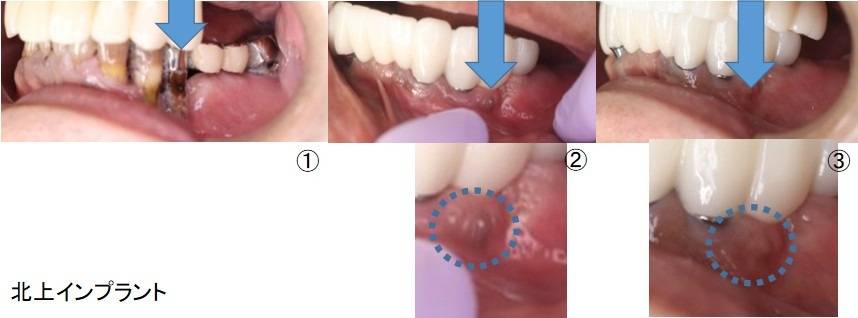

- 黒紫色

- 粘膜